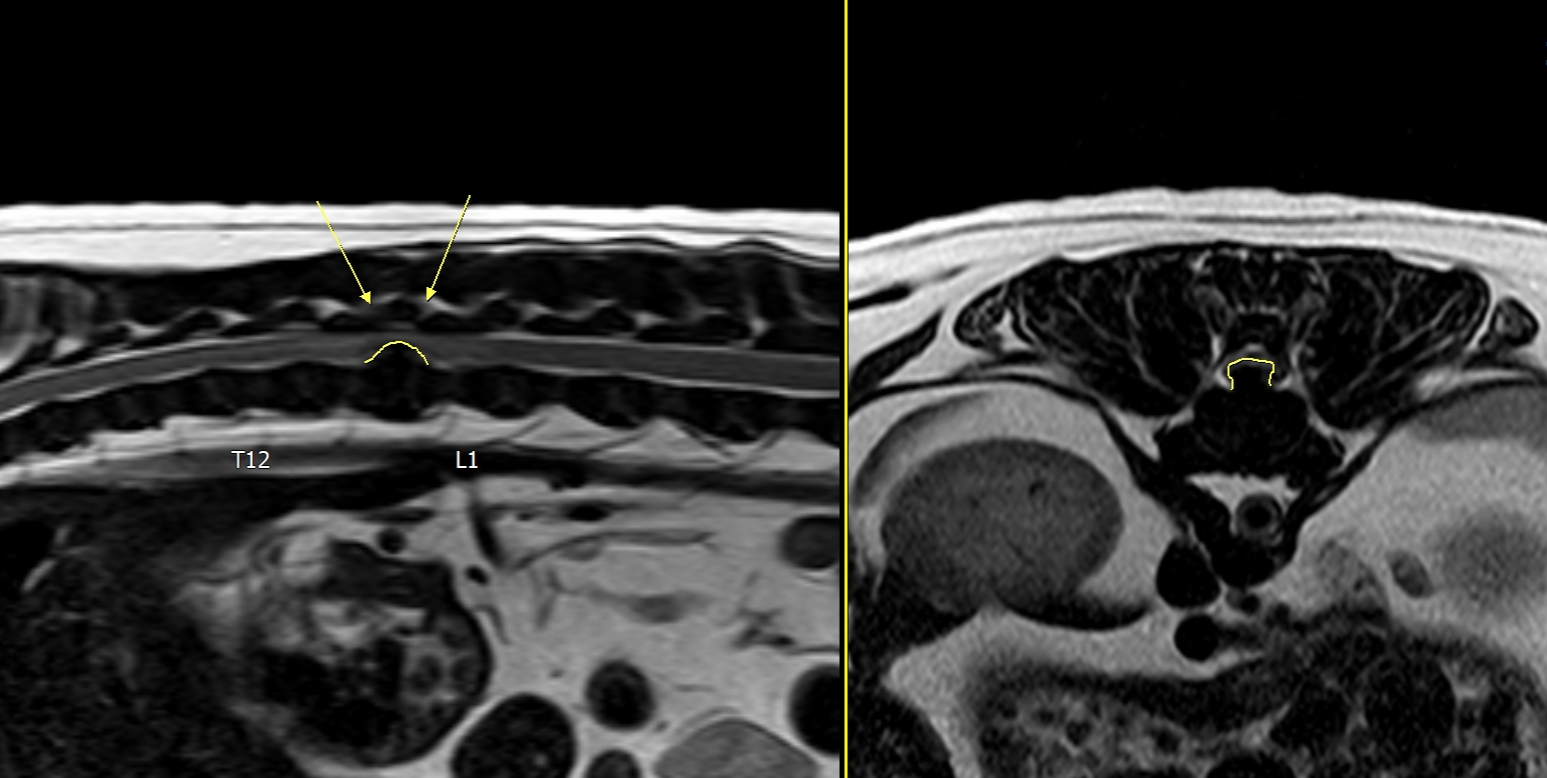

제가 키우고 있는 강아지는 말티즈와 푸들이 섞인 종으로 아주 건강하게 지내고 있었는데요. 어느날 갑자기 산책을 하고 나서 다리를 살짝 저는 증상이 보였습니다. 근처 야간까지 하는 병원으로 향했지만 이상이 없고 감기증상 같다며 감기약을 처방해주었어요. 그러나 다음날 증상은 더 심해졌고 갑작스럽게 깽 하는 소리와 함께 뒷 다리를 주저앉아버렸습니다. 빠르게 24시간 하는 2차 동물병원으로 향했고 mri결과 디스크판정을 받았습니다. 디스크는 총 5단계로 나눠져있는데 제가 키우는 반려견은 5단계로 가장 심각한 단계였습니다. 골든타임이 있다며 빠르게 수술을 해야한다고 하셨고 다음날 바로 수술을 들어갔습니다. 현재는 후지마비로 아직 걷지는 못하지만 열심히 재활을 하고있습니다. 이전에 조금이나마 지식이 있었다면 반려견에 건강을 책임질 수 있었을텐데.. 라는 아쉬움이 컸습니다. 이 글을 통해 누군가에게 도움이 되고 반려동물들이 모두 건강했으면 좋겠습니다.

* 허리 디스크가 의심되는 경우 조기 X선 검사 또는 MRI 검사로 확인합니다.